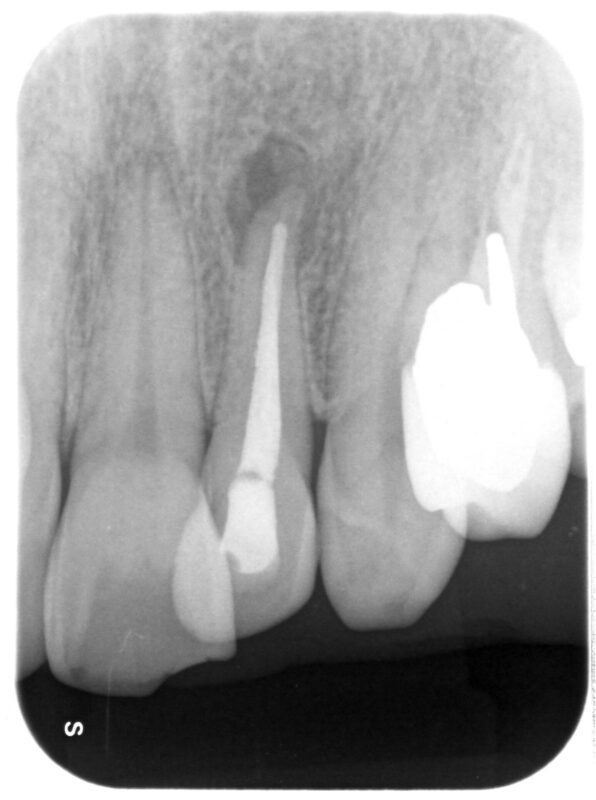

術前

歯根先端に影があります。

自覚症状はありませんが、サイナストラクト(絶えず歯肉を通して膿が出ています)が存在。

通常の根管治療を行いましたが改善しなかったので、マイクロスコープを用いて歯根先端を切除しまし

た。